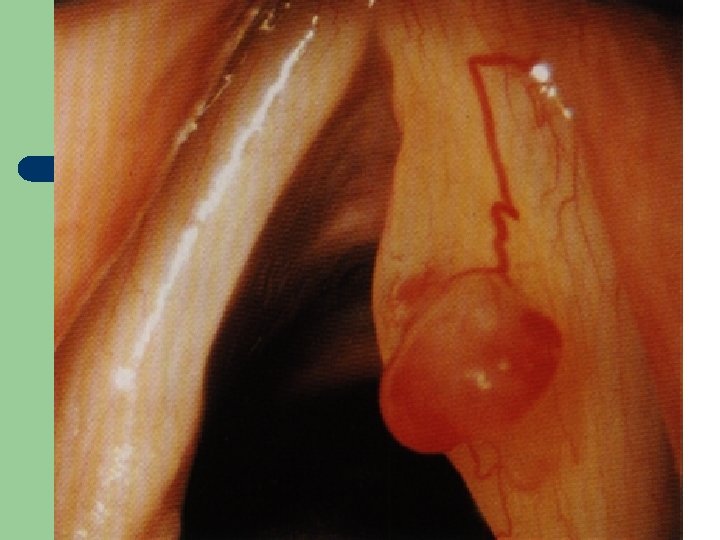

Vývoj dětské chraptivosti l 1. 2. 3. 4. Průvodním jevem při dětské chraptivosti je pokašlávání a pochrchlávání. Nález na hlasivkách postupuje takto: Hyperemické (překrvené hlasivky, Hypertrofické, vřetenovité zduření, hlasivkový uzávěr je neúplný a hlas má dyšnou příměs, ventrikulární řasy se začínají vyklenovat Zpěvácké uzlíčky, nejčastěji na hranicích přední a střední třetiny hlasivek Atrofie hlasivek až s podélnou rýhou, při fonaci nedomykavost uzávěru.

Hlasivkový uzlík l

Hlasivkový uzlík l

Hlasivkové uzlíky l